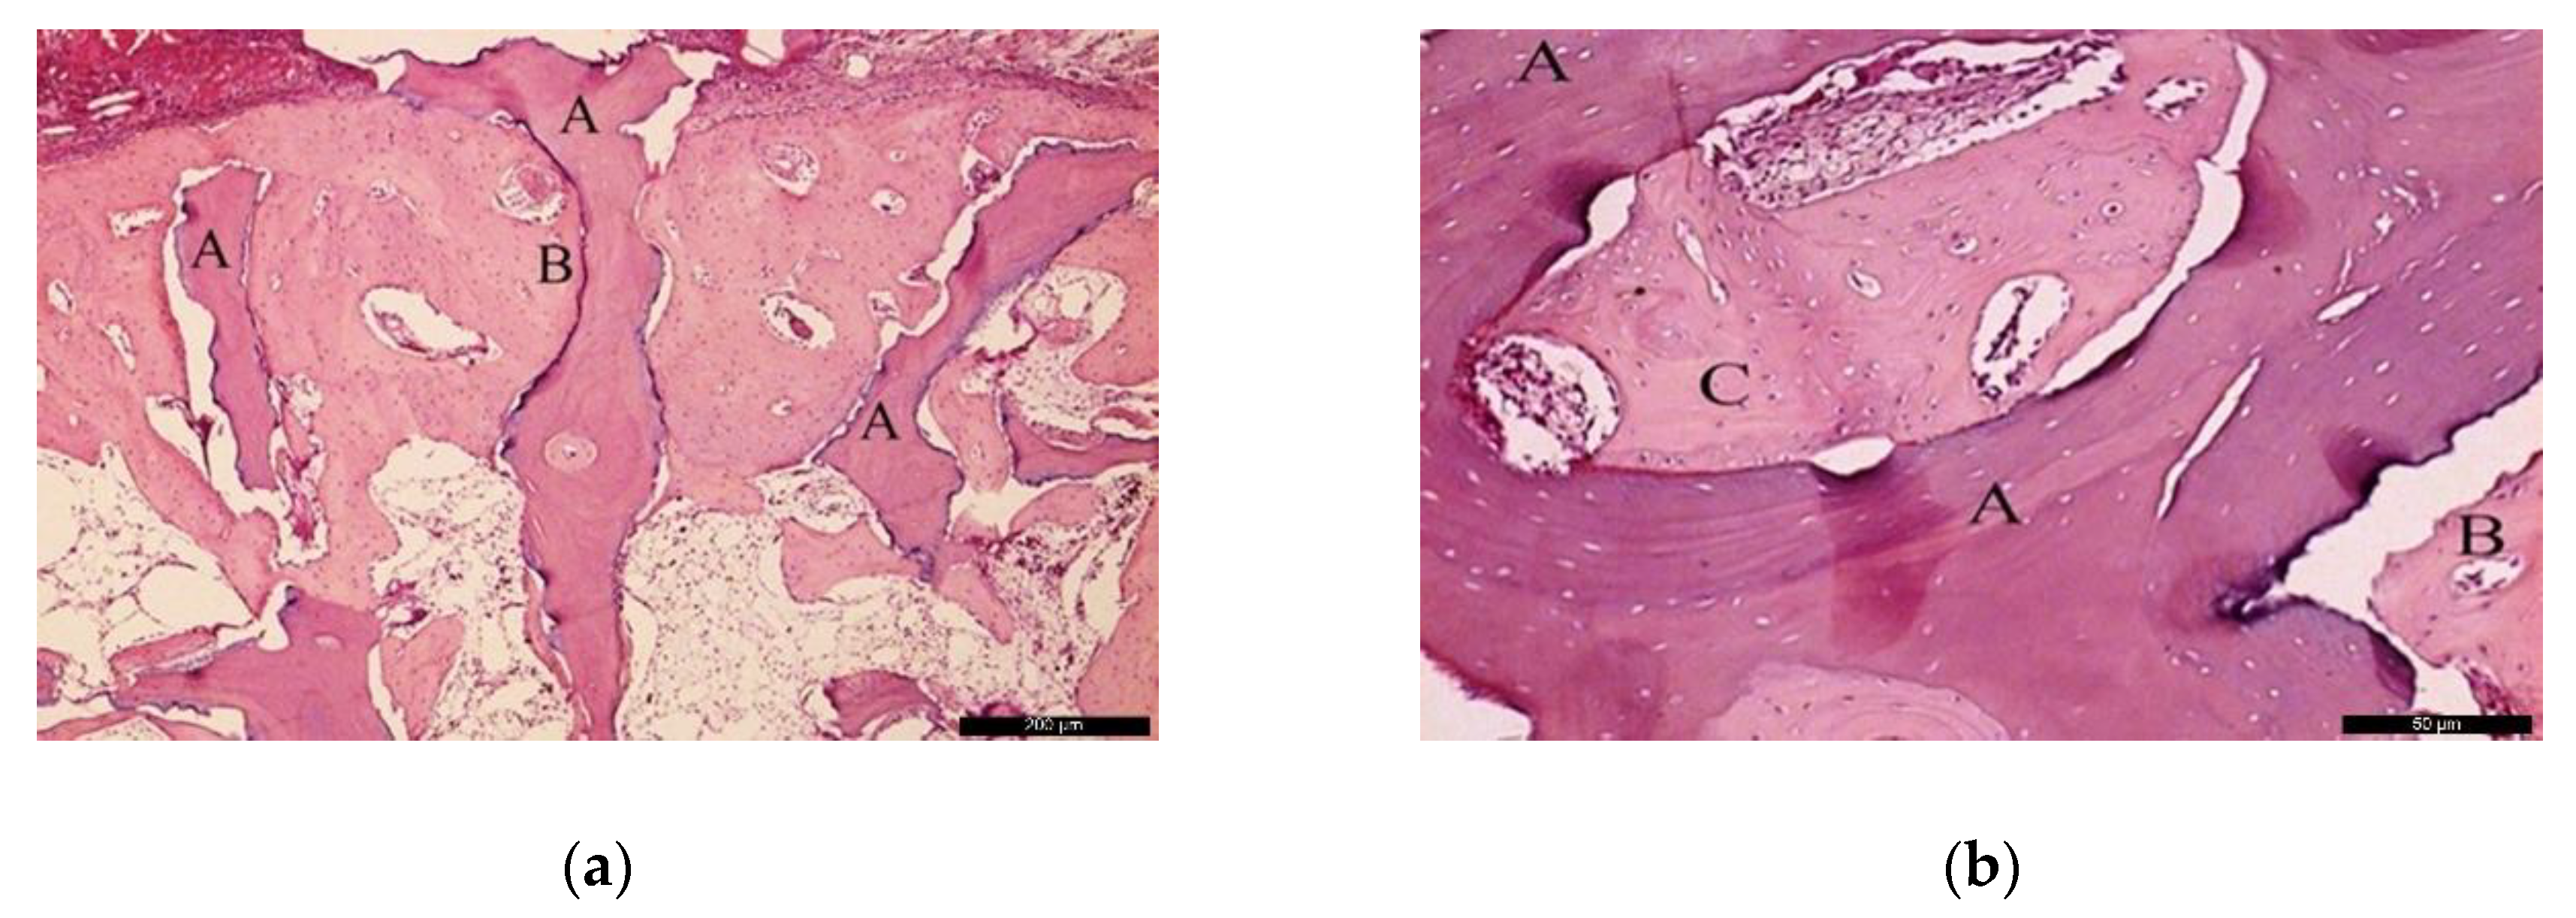

In the BG, after 60 post-operative days (Figure 6a), the biomaterial (A) was enwrapped by neoformed bone (B). In the inner part of the biomaterial, it was possible to observe islands of newly formed bone, highlighting the osteoconductivity capability of the bone substitute. At the same time, areas of resorption associated with volume loss were noticed, indicating high solubility of the biomaterial. At higher magnification (Figure 6b), it was possible to observe the bone substitute (A) on the recipient bed (B), and neoformed bone tissue (C).

Figure 6.

Histological analysis of the BG at 60 days. (a) Biomaterial (A) enwrapped by newly formed bone (B). Hematoxylin and eosin stain at a magnification 40×; (b) Biomaterial (A) on the recipient bed (B), and newly formed bone (C). Hematoxylin and eosin stain at a magnification 125×.